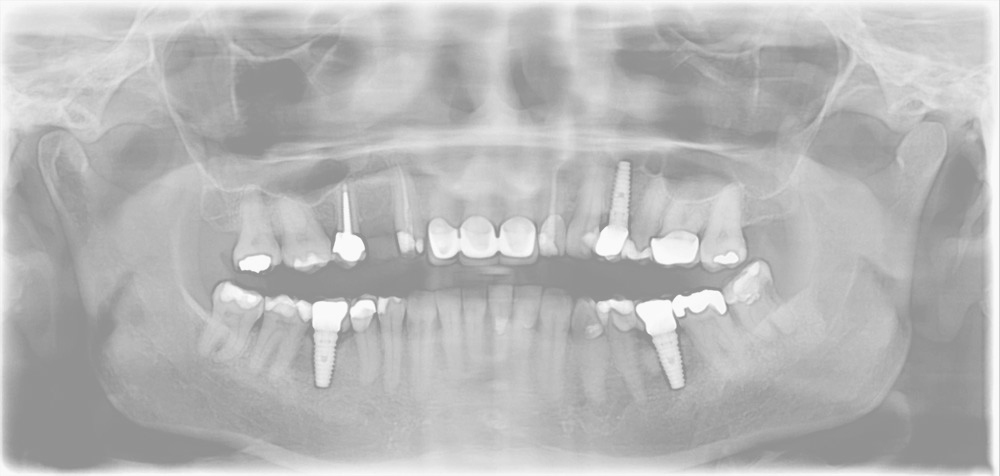

Dr. Rabinowitz, DMD, FICOI has 25 years of experience as a dento-legal consultant and expert witness for dental, oral surgery, implant, prosthodontic, crown and bridge, dental implant, nerve injury, periodontal and endodontic – root canal cases. He advises legal counsel for dentists, dental schools, hospitals and plaintiffs on issues of standard of care, misdiagnosis, treatment failure and complications.

Dr. Rabinowitz has been an actively practicing dentist for over 35 years, with residency and fellowship training and comprehensive clinical and teaching experience in restorative and implant dentistry, oral surgery, crown and bridge prosthodontics, endodontics, soft tissue and bone grafting, periodontics and intravenous sedation.